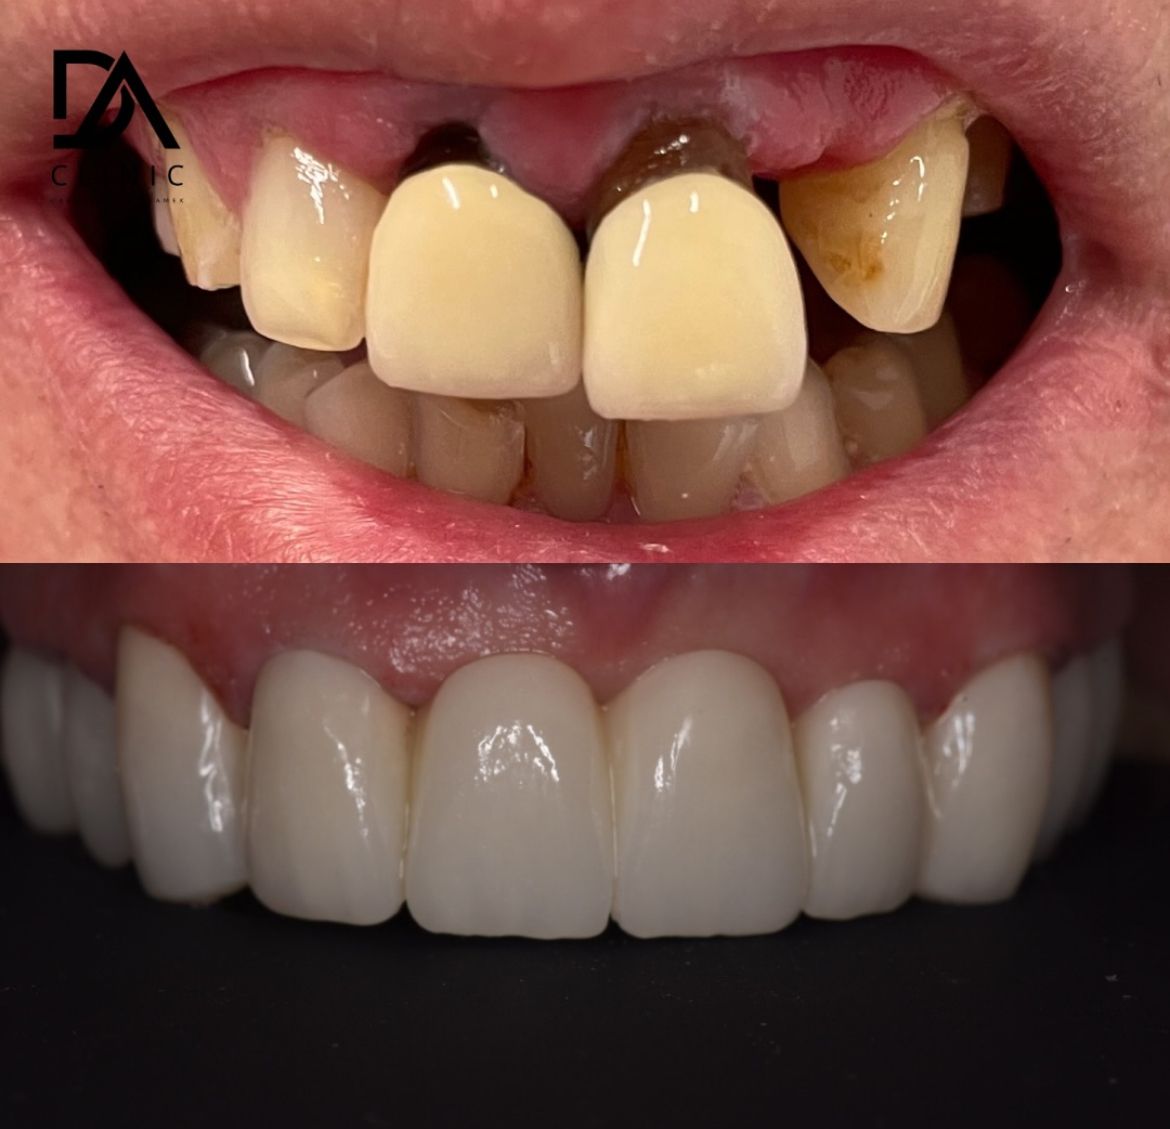

- protetyka (korony ceramiczne (cerkon, E-max), licówki, mosty, protezy ruchome, korony na teleskopach, inlay, onlay, overlay, endkorony);